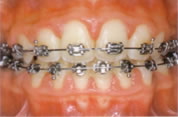

○ブラケット+ワイヤー(金属ブレース)

もっとも代表的な、いわゆるはり金の装置です。ワイヤーの力で個々の歯を動かします。ブラケットは接着剤で歯に固定されているので取り外しはできません。